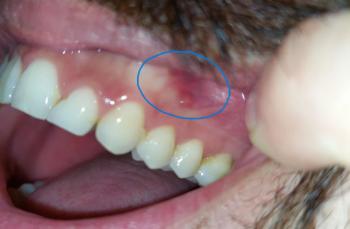

What Is Seen in This Case?

The image shows visible decay on back teeth (molars), with damaged tooth structure and discoloration. The surrounding gum tissue appears slightly irritated, which may indicate early inflammation caused by trapped bacteria.

Based on the visual findings, the most likely conditions include:

Dental caries (tooth decay) on molars

Possible decay reaching the dentin layer

Early gum inflammation near the affected teeth